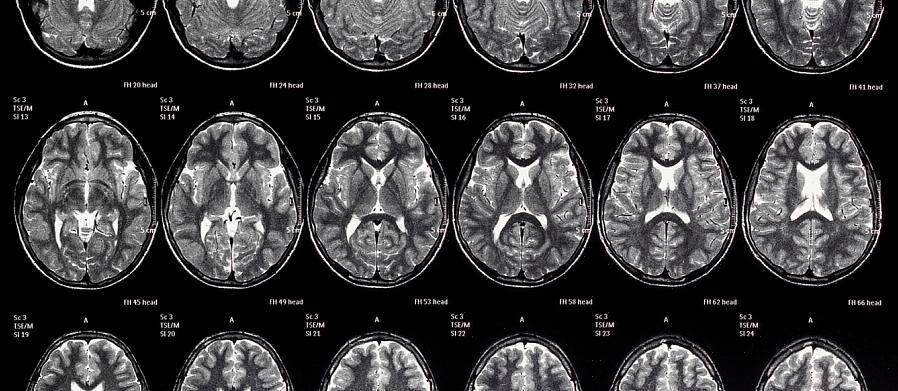

האם זה נכון שעוני משנה את המוח האנושי? ובכן, רבים מחקרי המוח של 50 השנים האחרונות התרכזו בחקר ההשפעות של סביבה מועשרת. הם גילו שגירוי חברתי ואינטלקטואלי גדול יותר מוביל לשינויים מבניים ותפקודיים במוח.

בהתחשב בעובדה זו, החוקרים החלו לחקור מה קורה במצב הפוך. לפיכך, הם הבחינו כי מחסור במשאבים ועוני משנים גם את המוח האנושי.

המחקרים הראשונים התמקדו בניסיון לגלות כיצד הבדלים סוציו-אקונומיים משתקפים בהתנהגות ובקוגניציה של האדם. אחרים, על איתור רשתות המוח, התפקודים והמבנים השונים לפי רמות סוציואקונומיות. למרות זאת, מדענים עדיין אינם יודעים כיצד בדיוק מתרחשים ההבדלים הללו. עם זאת, יש מספיק ראיות כדי לאשר שעוני משנה את המוח האנושי.

ממצאים אלו מתייחסים בעיקר לאוכלוסיית הילדים מכיוון שמוח מתפתח רגיש יותר לגורמים חיצוניים.

גורמים סביבתיים, בנוסף לגורמים גנטיים, מניעים את התפתחות המוח. לפיכך, הרמה הסוציו-אקונומית של האדם בהחלט יכולה להשפיע על תקופה זו.

שפה היא אחת היכולות הקשורות ביותר לרמה החברתית-כלכלית במהלך הילדות. מחקר בהקשר זה הראה כיצד ילדים עניים יותר מראים פחות התמחות באזורי המוח הנוגעים לשפה.

באשר לזיכרון, לילדים העניים ביותר יש היפוקמפוס קטן יותר. והאפקט הזה נמשך בחמשת העשורים הבאים, ללא קשר לתנאים הסוציו-אקונומיים בבגרות.

באופן דומה, האמיגדלה היא מבנה מוחי הנוגע לעיבוד רגשי, למידה ומוטיבציה. במובן זה, לילדים העניים ביותר יש אמיגדלה קטנה יותר, שיכולה להשתנות ולהתרגם לוויסות רגשי לקוי.

בנוסף, כשמדובר בתפקודים ניהוליים (תהליכים קוגניטיביים מורכבים יותר כמו קבלת החלטות או תכנון), מחסור בגירוי ומשאבים מוביל לשינויים ולחסכים.

כמו בתהליכים הקודמים, קיים קשר בין רמות סוציו-אקונומיות נמוכות יותר וביצועי מנהלים גרועים יותר ובנוסף, נפח נמוך יותר באזורי המוח המעורבים.